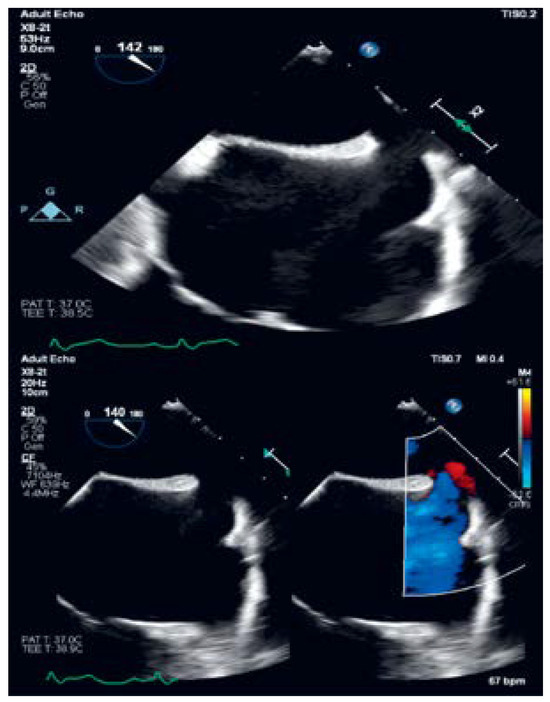

Superior Sinus Venosus Atrial Septal Defect with Partial Anomalous Pulmonary Venous Drainage—Minimally Invasive Approach—Case Report

The atrial septal defect is, after bicuspid aortic valve disease, the most common congenital cardiac disease present in the adult population. The most common atrial septal defects are the ostium secundum type (75–80%), followed by the ostium primum type (15%). The sinus venosus [...] Read more.

The atrial septal defect is, after bicuspid aortic valve disease, the most common congenital cardiac disease present in the adult population. The most common atrial septal defects are the ostium secundum type (75–80%), followed by the ostium primum type (15%). The sinus venosus atrial septal defects (SV-ASD), defined as a communication in the posterior part of the interatrial septum, account for about 5 to 10% of atrial septal defects. Approximately 90% of SV-ASDs are associated with partial anomalous pulmonary venous drainage (PAPVD). The minimally invasive approach has gained ground in the treatment of ASDs, especially those of the ostium secundum type. The sinus venosus type is a relatively uncommon form of ASD, which, when associated with a PAPVD, is considered a complex cardiac malformation, and is usually treated in a classical manner, through median sternotomy. We describe the case of a 45-year-old woman diagnosed in adolescence with SV-ASD with PAPVD, who successfully underwent minimally invasive repair with fresh autologous pericardial patch reconstruction through an anterolateral mini-thoracotomy incision. The patient presented with shortness of breath and fatigue after heavy exertions, episodes of paroxysmal nocturnal dyspnea, palpitations during effort and at rest, and had a history of syncope dating from 17 years previously. Echocardiography revealed an SV-ASD with PAPVD in the right atrium and the intraoperative examination discovered that both right pulmonary veins were draining into the superior vena cava. Full article

Show Figures